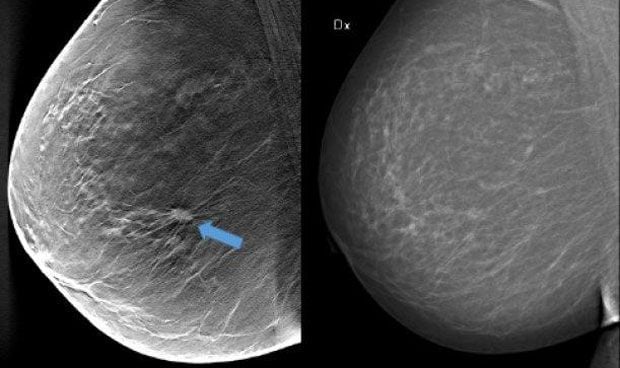

Diferencia entre una mamografía en 3D (izquierda) y una tradicional.

Y es que, en la mamografía tradicional todo el tejido mamario se captura en una sola imagen, mientras que en la de 3D se toman varias imágenes de rayos X de baja dosis del seno desde diferentes ángulos, lo que aumenta la posibilidad de detectar tumores. Además, la dosis de radiación puede reducirse en ciertas circunstancias.